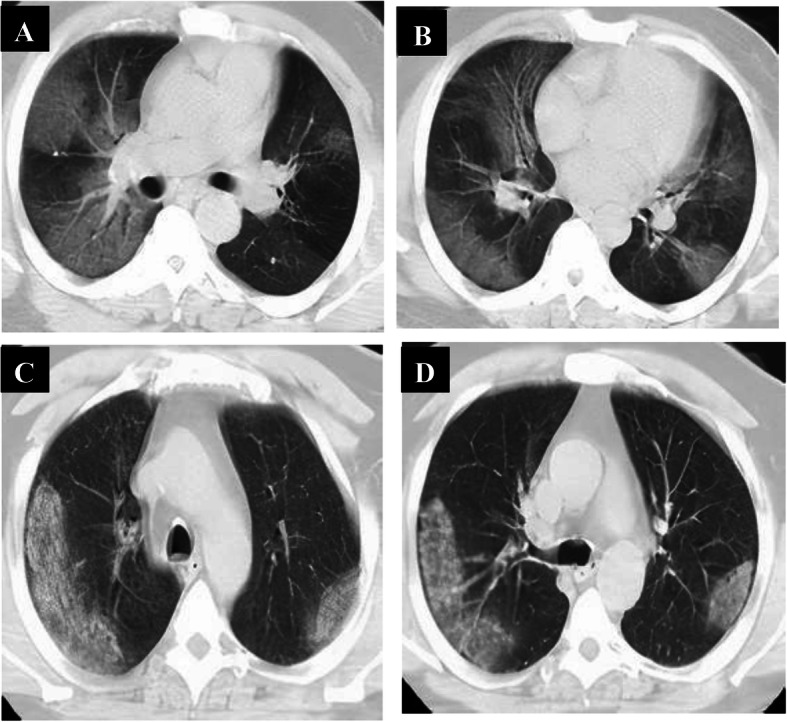

Follow-up chest CT studies were done for 108 patients in the intermediate phase after 7–8 days from onset of symptoms, and 8 patients were missed due to death. We reported positive CT findings in all of them; CT lung abnormalities were progressed than initial CT; GGO only in 9 patients, combined GGO and consolidation in 99 patients, crazy-paving in 14 patients, reversed halo in 8 patients, and linear consolidation in 32 patients. Peripheral distribution was noted in 12 patients, and diffuse distribution in 96 patients. 108 had bilateral affection with three lobes of affection in 30 patients, 4 lobes of affection in 41 patients, and 5 lobes of affection in 37 patients. Total lung severity score is as follows: 26 patients with score 13, 21 patients with score 15, 27 patients with score 16, 14 patients with score 18, and 20 patients with score 19 (mean of 15.89 ± 2.13) (Fig. 7).

Fig. 7.

A 51-year-old male patient complaining of cough and dyspnea (severe symptoms). Non-contrast axial chest CT (a, b) 6 days from the onset of symptoms (intermediate phase) revealed multiple patchy areas of ground-glass opacity seen scattered at both lungs: peripheral in distribution. With the persistence of symptoms, follow-up chest CT (c, d) 9 days revealed multiple patchy areas of consolidation seen scattered at both lungs: peripheral in distribution